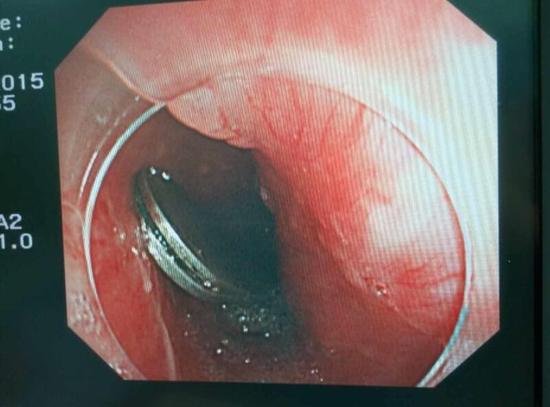

手術(shù)中,范醫(yī)生通過胃鏡準確發(fā)現(xiàn)了胃里的鑷子。但讓他驚訝的是,在華先生胃底竟然還躺著三個被腐蝕了的打火機,打火機的金屬部件都已經(jīng)不見了。

隨后,范醫(yī)生先用圈套器套取出了長10厘米的鑷子,再一個一個地取出了打火機。整個取出過程小心謹慎而又一氣呵成,只用了不到10分鐘。

“真的是太危險了?!狈夺t(yī)生表示,鑷子前端比較尖銳,一旦刺穿胃前壁,又有可能刺破肝臟,引發(fā)臟器受損和大出血。而打火機在胃內(nèi)酸性胃液腐蝕后,不 僅塑料外殼有毒,打火機內(nèi)的燃料一旦發(fā)生泄露會有灼傷胃腸道的危險。打火機頭端還有尖銳金屬部件,若嵌頓或劃傷腸道會誘發(fā)腸梗阻、腸穿孔、消化道出血等嚴 重并發(fā)癥。